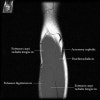

2. Axial section

1) The tendons of the Biceps Brachii and Brachiallis muscles transversely as they insert onto the Radius and Ulna respectively. 2) The distal Triceps tendon is also well evlauated in this plane.